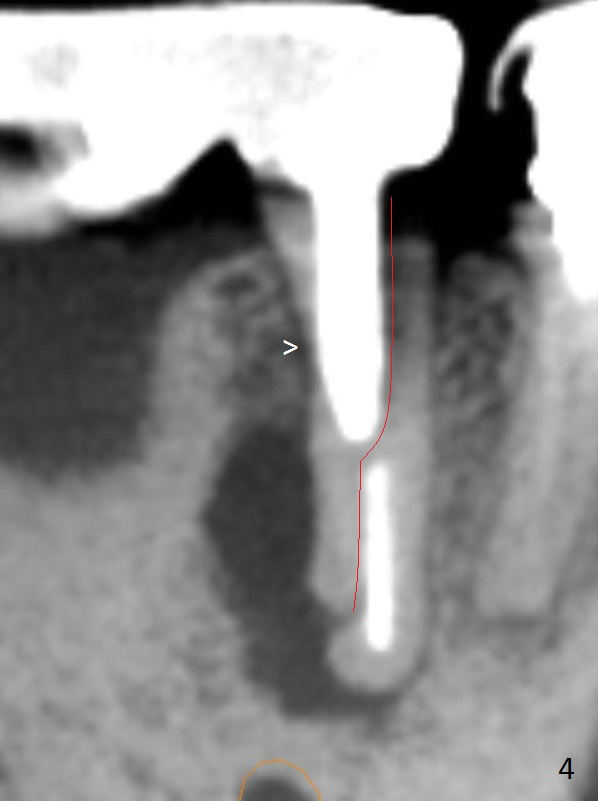

A 50-year-old man has pain and swelling buccal to the tooth #29 with large distal radiolucency (Fig.1 *). The bridge will be sectioned between #30 and 31. The mesial segment of the bridge is expected to separate from #29 post space; the mesial abutment is presumed to have vertical fracture (Fig.4 red line or root perforation due to oversized post (>)). After intraligamental injection, extraction and no Antibiotic treatment, a narrow long implant (Fig.6,7: 3.8x15 or 13 mm) will be placed as mesial and lingual as possible to avoid the buccal bony defect (Fig.5 >; repaired with Osteotape or PRF membrane) and the Mental Loop (Fig.1 >).